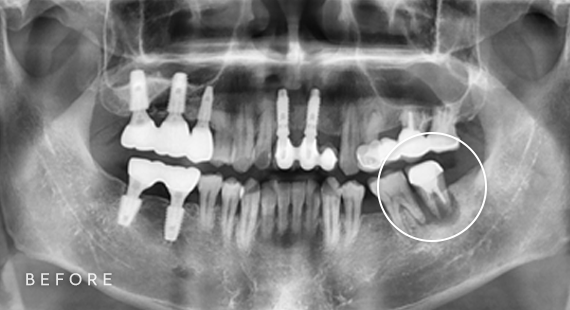

임플란트

사랑니 발치